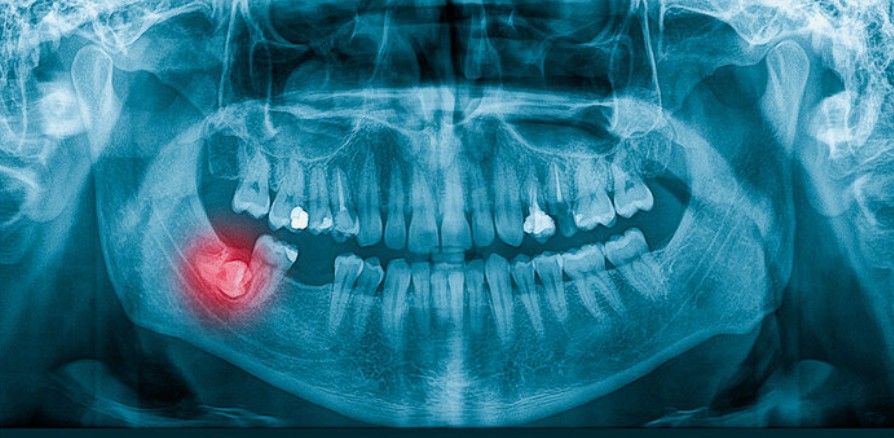

Sau 25 tuổi, mật độ xương hàm đã đặc hơn, khiến việc nhổ răng mất nhiều thời gian hơn. Ngoài ra, vị trí răng khôn lúc này có thể đã nằm sát dây thần kinh hàm dưới hoặc xoang hàm trên, nên cần chụp phim X-quang hoặc CBCT kỹ lưỡng trước khi phẫu thuật.

Trước khi nhổ, bác sĩ thường chỉ định chụp phim X-quang hoặc CBCT để đánh giá hướng mọc, vị trí chân răng và khoảng cách với dây thần kinh. Đây là bước quan trọng giúp bác sĩ lập kế hoạch nhổ an toàn và chính xác.